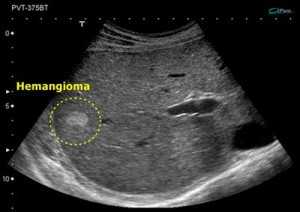

В большинстве случаев гемангиома обнаруживается случайно, чаще всего во время ультразвукового исследования, так как у нее нет специфических клинических признаков, за исключением случаев крупных опухолей.

Диагностика и дифдиагностика

Поскольку данная патология не имеет специфических признаков, перечисленные симптомы не могут однозначно указать врачу на наличие сосудистой опухоли, так как можно выдвинуть множество предположений. В таких случаях обычно назначается наиболее доступное исследование печени – ультразвуковая диагностика, на основе которой можно установить предварительный диагноз.

Гемангиома печени на УЗИ может проявляться по-разному в зависимости от эхоструктуры печени:

- как более светлое, почти белое образование, что называется повышенной эхогенностью;

- как более темное образование, что обозначается как пониженная эхогенностью;

- как образование с такой же эхоплотностью, как и сама печень.

Определение последнего варианта при ультразвуковом исследовании печени может быть затруднительным. Однако в некоторых патологических состояниях, например, при отеке тканей органа, такие опухоли могут стать заметными. Это связано с тем, что при отеке ткань печени становится более темной, а гемангиома выглядит относительно светлой.

Иногда можно обнаружить атипичную форму сосудистой опухоли, которая характеризуется отложением кальция и наличием крупных полостей, заполненных кровью.

Форма опухоли чаще всего округлая, но может быть и овальной. Контуры четкие, могут быть мелко- или крупноволнистыми, что зависит от размера очага. Структура часто неоднородная, с участками различной плотности, что указывает на наличие полостей.